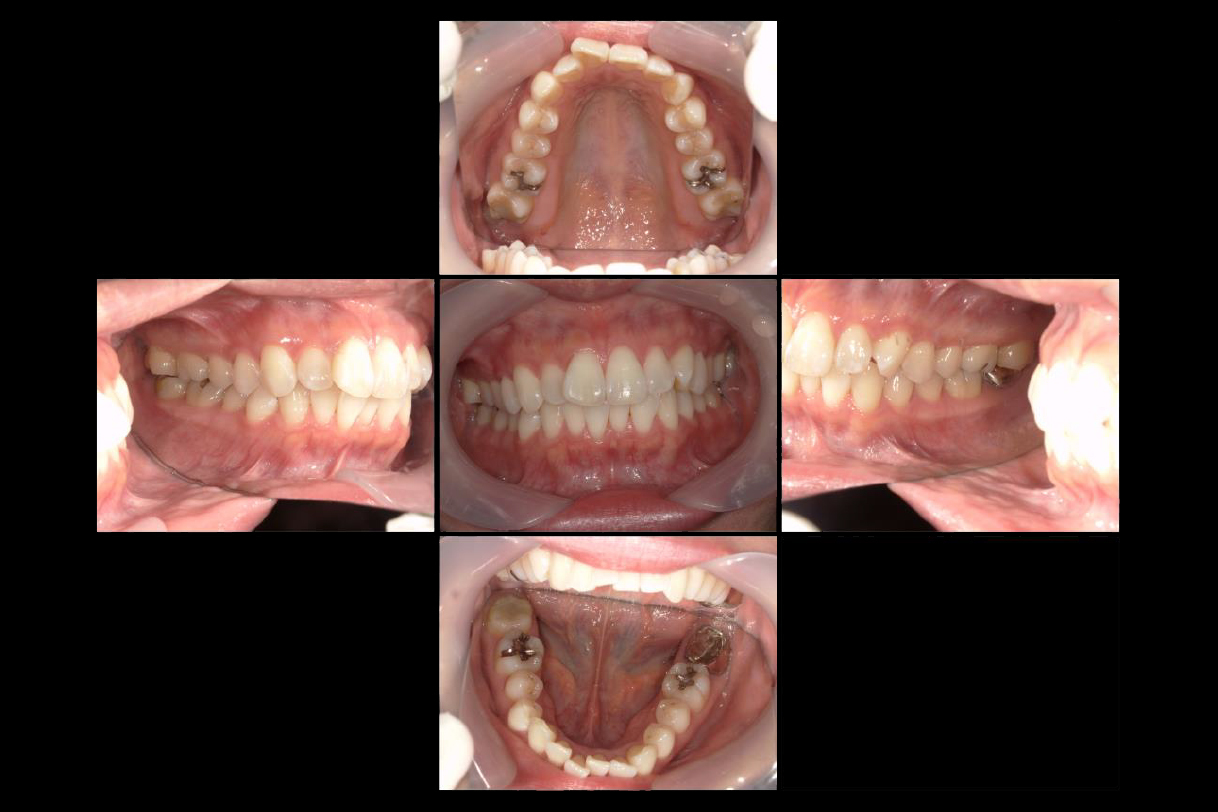

初診時年齢:20代女性

治療:前歯部矯正

治療法:マウスピース型矯正装置(インビザライン)

治療期間:1年1ヶ月

費用:462,000円(税込)

リスク・副作用:装置装着による違和感、歯の移動時の痛み